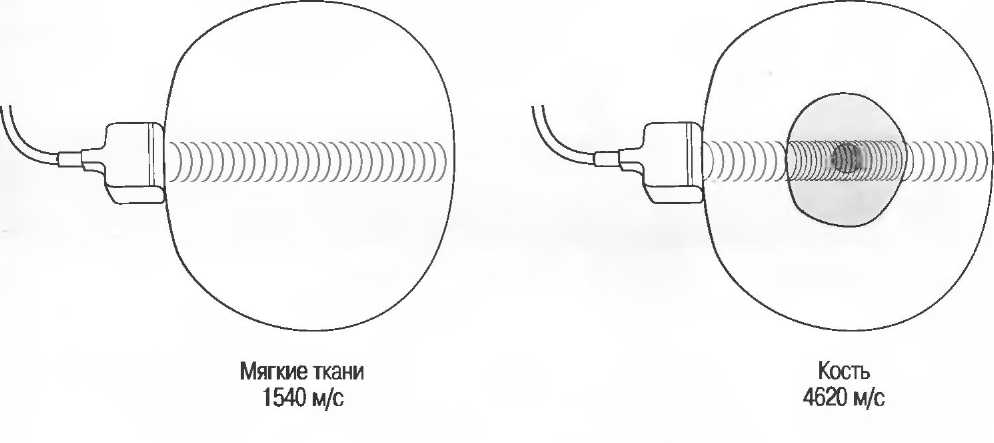

Ультразвуковые волны распространяются в мягких тканях как продольные волны. Молекулы вибрируются и передают энергию следующей молекуле, таким образом ультразвуковая энергия распространяется по телу. Средняя скорость распространения ультразвука для мягких тканей составляет 1540 м/с.

Ткани очень отличаются по характеру их взаимодействия с ультразвуком. Например, кости скелета и газ в кишечнике или легких значительно отличаются от мягких тканей. Когда ультразвуковые волны встречают на своем пути кость или газ, они в большей степени отражаются или преломляются. Поэтому практически невозможно эффективно использовать ультразвук при наличии большого количества газа в кишечнике: при исследовании малого таза необходимо как можно полнее наполнять мочевой пузырь для того, чтобы приподнять кишечник и убрать его с пути прохождения ультразвуковых волн. Из-за наличия воздуха практически невозможно исследовать легкие, однако можно визуализировать жидкость в плевральной полости или опухоль, соприкасающуюся со стенкой грудной полости.

Кости скелета очень интенсивно отражают ультразвук, поэтому внутренняя структура кости либо другой сильно кальцинированной структуры не видна. В результате этого получение изображения через кости черепа или другие кости у взрослых невозможно (рис. 5).